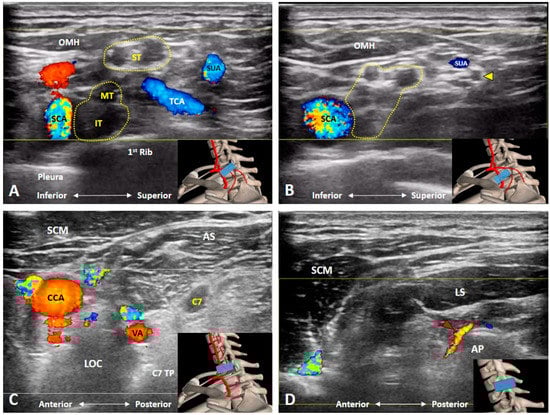

2. Anatomy

3. Imaging for Normal BP

3.5. Which Vascular Structure(s) Should We Be Aware Of?

3.6. Which Branches of the BP Can Be Seen in the Cervical Region?

4.5. Thoracic Outlet Syndrome